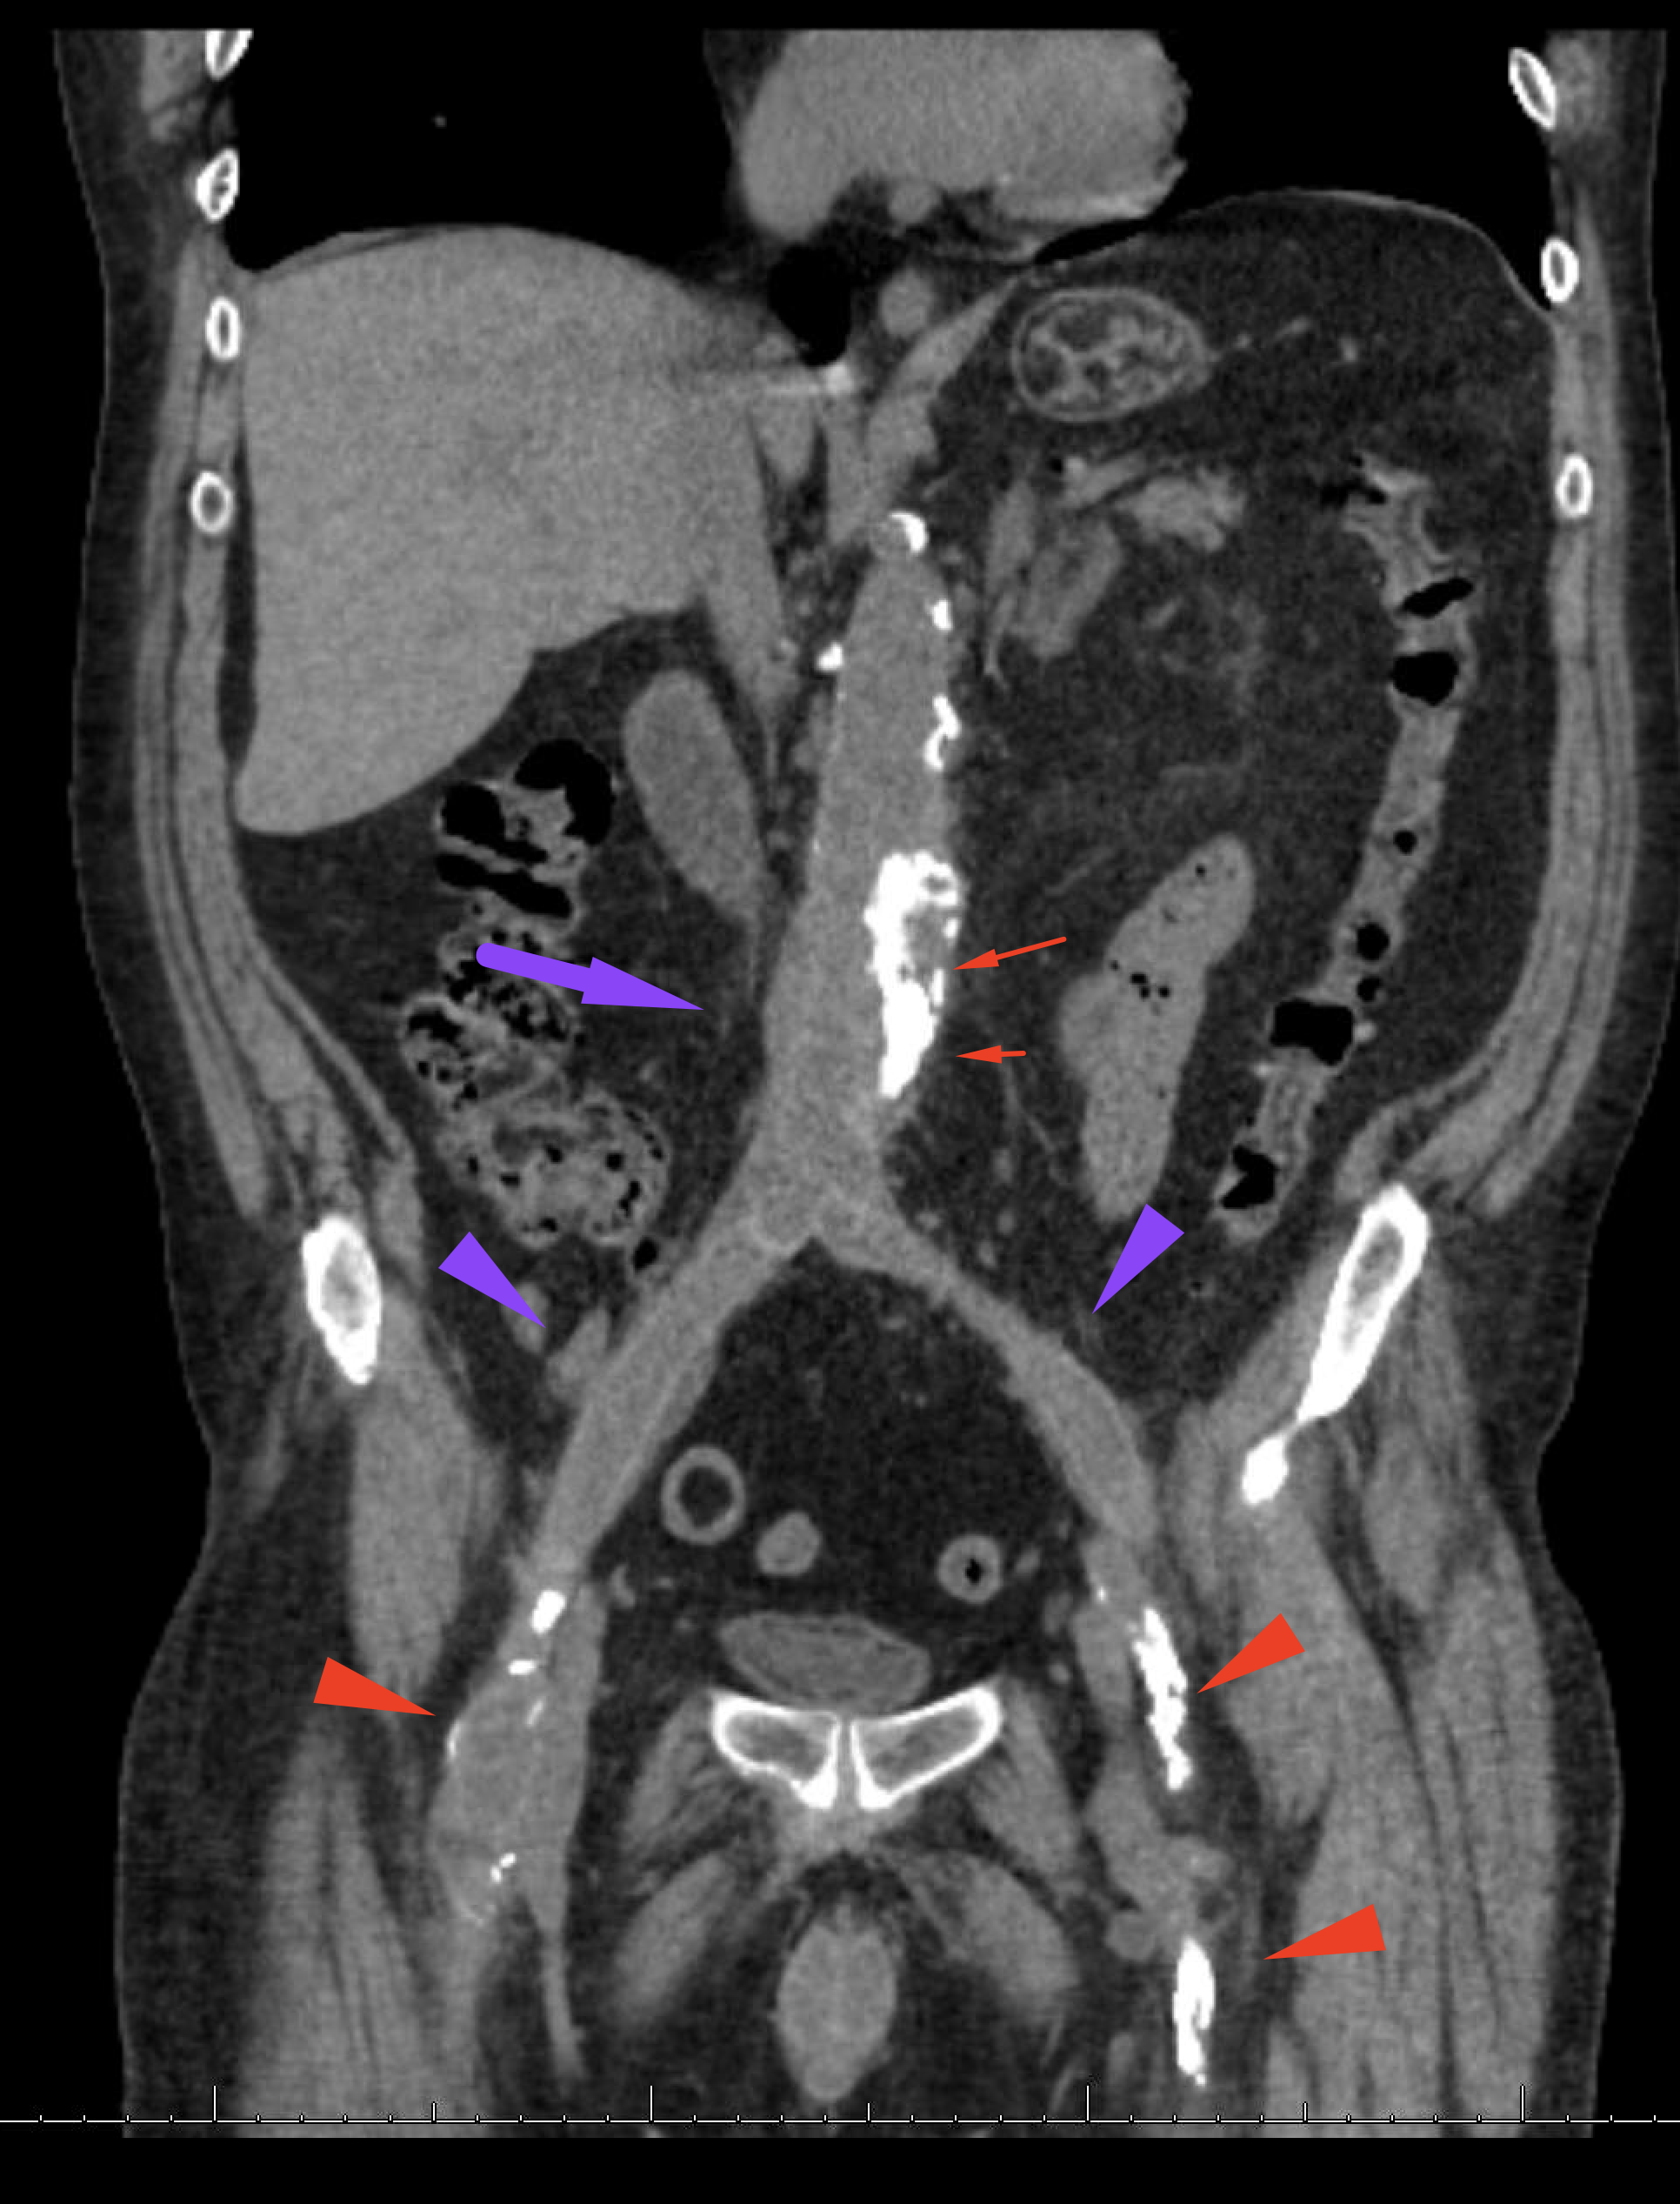

Age: 66

Sex: Male

Indication: Hematochezia

Radiotracer: Tc99m labeled RBCs

Sample ReportNo evidence of active GI bleeding during the course of this study.